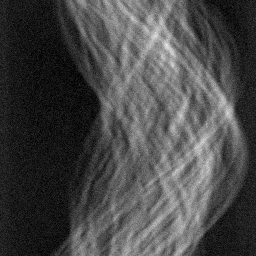

Figure 2: Qualitative inpainting results on TomoBank (lines 1 to 2) and LoDoPaB (lines 3 to 4) with random mask (ratio = 0.8) at 1024×\times1024 resolution. Odd columns and even columns show the sinograms and reconstructed images, respectively.

Inpainting Quality. Tab 2 summarizes accuracy results. At 2048×\times2048 resolution, HiSin achieves the best performance among all baselines while remaining memory-efficient, demonstrating its ability to extend high-quality inpainting to resolutions where other diffusion models fail. At 1024×\times1024, HiSin delivers accuracy comparable to its computation-intensive counterpart RePaint, showing that our optimizations do not compromise fidelity at moderate scales. Compared to DiffIR and HiDiffusion, HiSin consistently achieves higher SSIM and PSNR across mask ratios, with improvements up to +0.03 SSIM and +1.8 dB PSNR. Fig 2 visualizes sinogram inpainting and reconstructed images, where HiSin produces nearly indistinguishable results from RePaint. These findings confirm that HiSin fundamentally extends diffusion-based inpainting to 2048×\times2048 resolution in a more memory- and runtime-efficient manner.